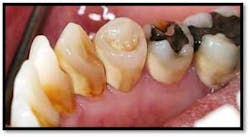

Treatment: FM Perioscopy completed in two, 2-hour sessions with local anesthetic and micro ultrasonics. No hand instruments are necessary during Perioscopy.

Note: When instrumenting “blindly,” the end point is unknown and debris is left behind. Visualization via the Perioscopy System ensures effective treatment is rendered because the bioburden is completely removed. Ultrasonic instrumentation is not only effective and efficient for thorough bacterial removal, but is an easier therapy to tolerate for the patient, with less sensitivity post treatment.9 months Post Treatment: